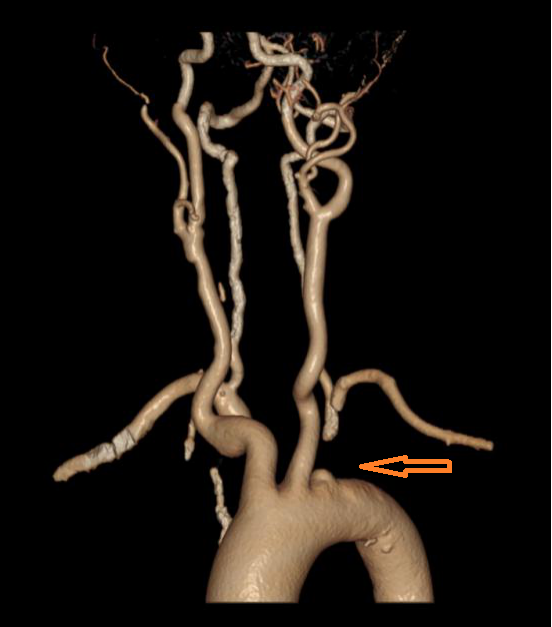

图1左侧锁骨下动脉闭塞,箭头所指               图2 经右侧椎动脉造影:可见血流自左侧椎动脉向远